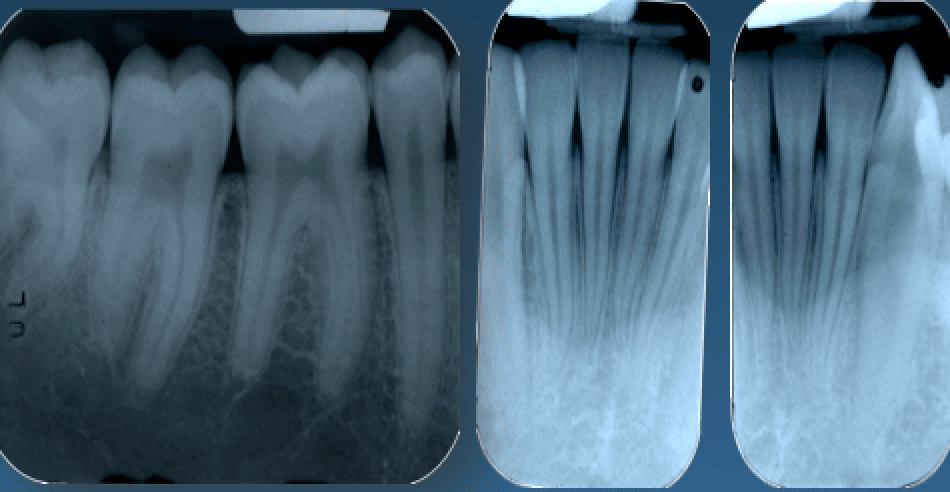

Questo importante esame deve essere sempre e comunque validato da radiografie endorali (non ortopantomografia), essenziali per potersi avvicinare quanto più possibile alla verità clinica.

Quante volte i pazienti mi hanno chiesto di non fare radiografie, non capendo che esse permettono numerose considerazioni che, insieme all’esame clinico parodontale del sondaggio, porteranno ad un piano di trattamento con o senza chirurgie, con o senza estrazioni, con più o con meno costi? Vi sembra poco tutto questo?

Tutto ciò consente di fare ora una corretta diagnosi, di avere indicazioni cliniche per il futuro piano di trattamento (che può significare fare o meno chirurgie) e di poter controllare, ripetendo radiografie e sondaggi nel tempo, l’andamento osseo della malattia parodontale.